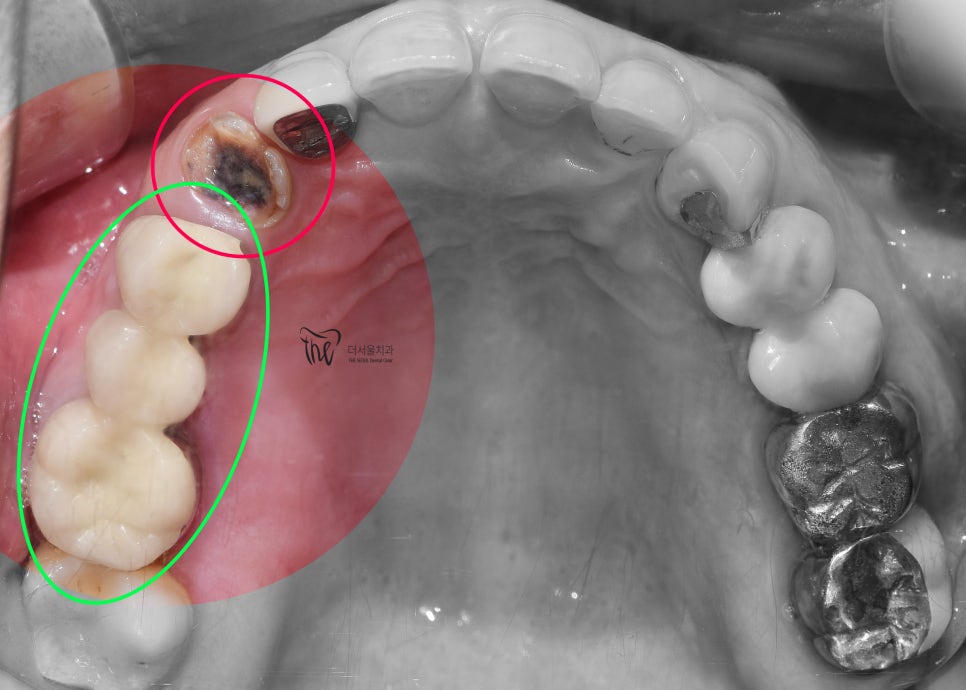

정면에서 보면, 치질의 일부는 남아있죠?

뿌리만 남아있는 채 더서울치과에 오셨었습니다.

그리고, 씹는면에서 보게 되면 치수속이

까맣게 변색이 되어있는 것을 볼 수 있습니다.

즉.. 이미 많이 썩을대로 썩었다는거.